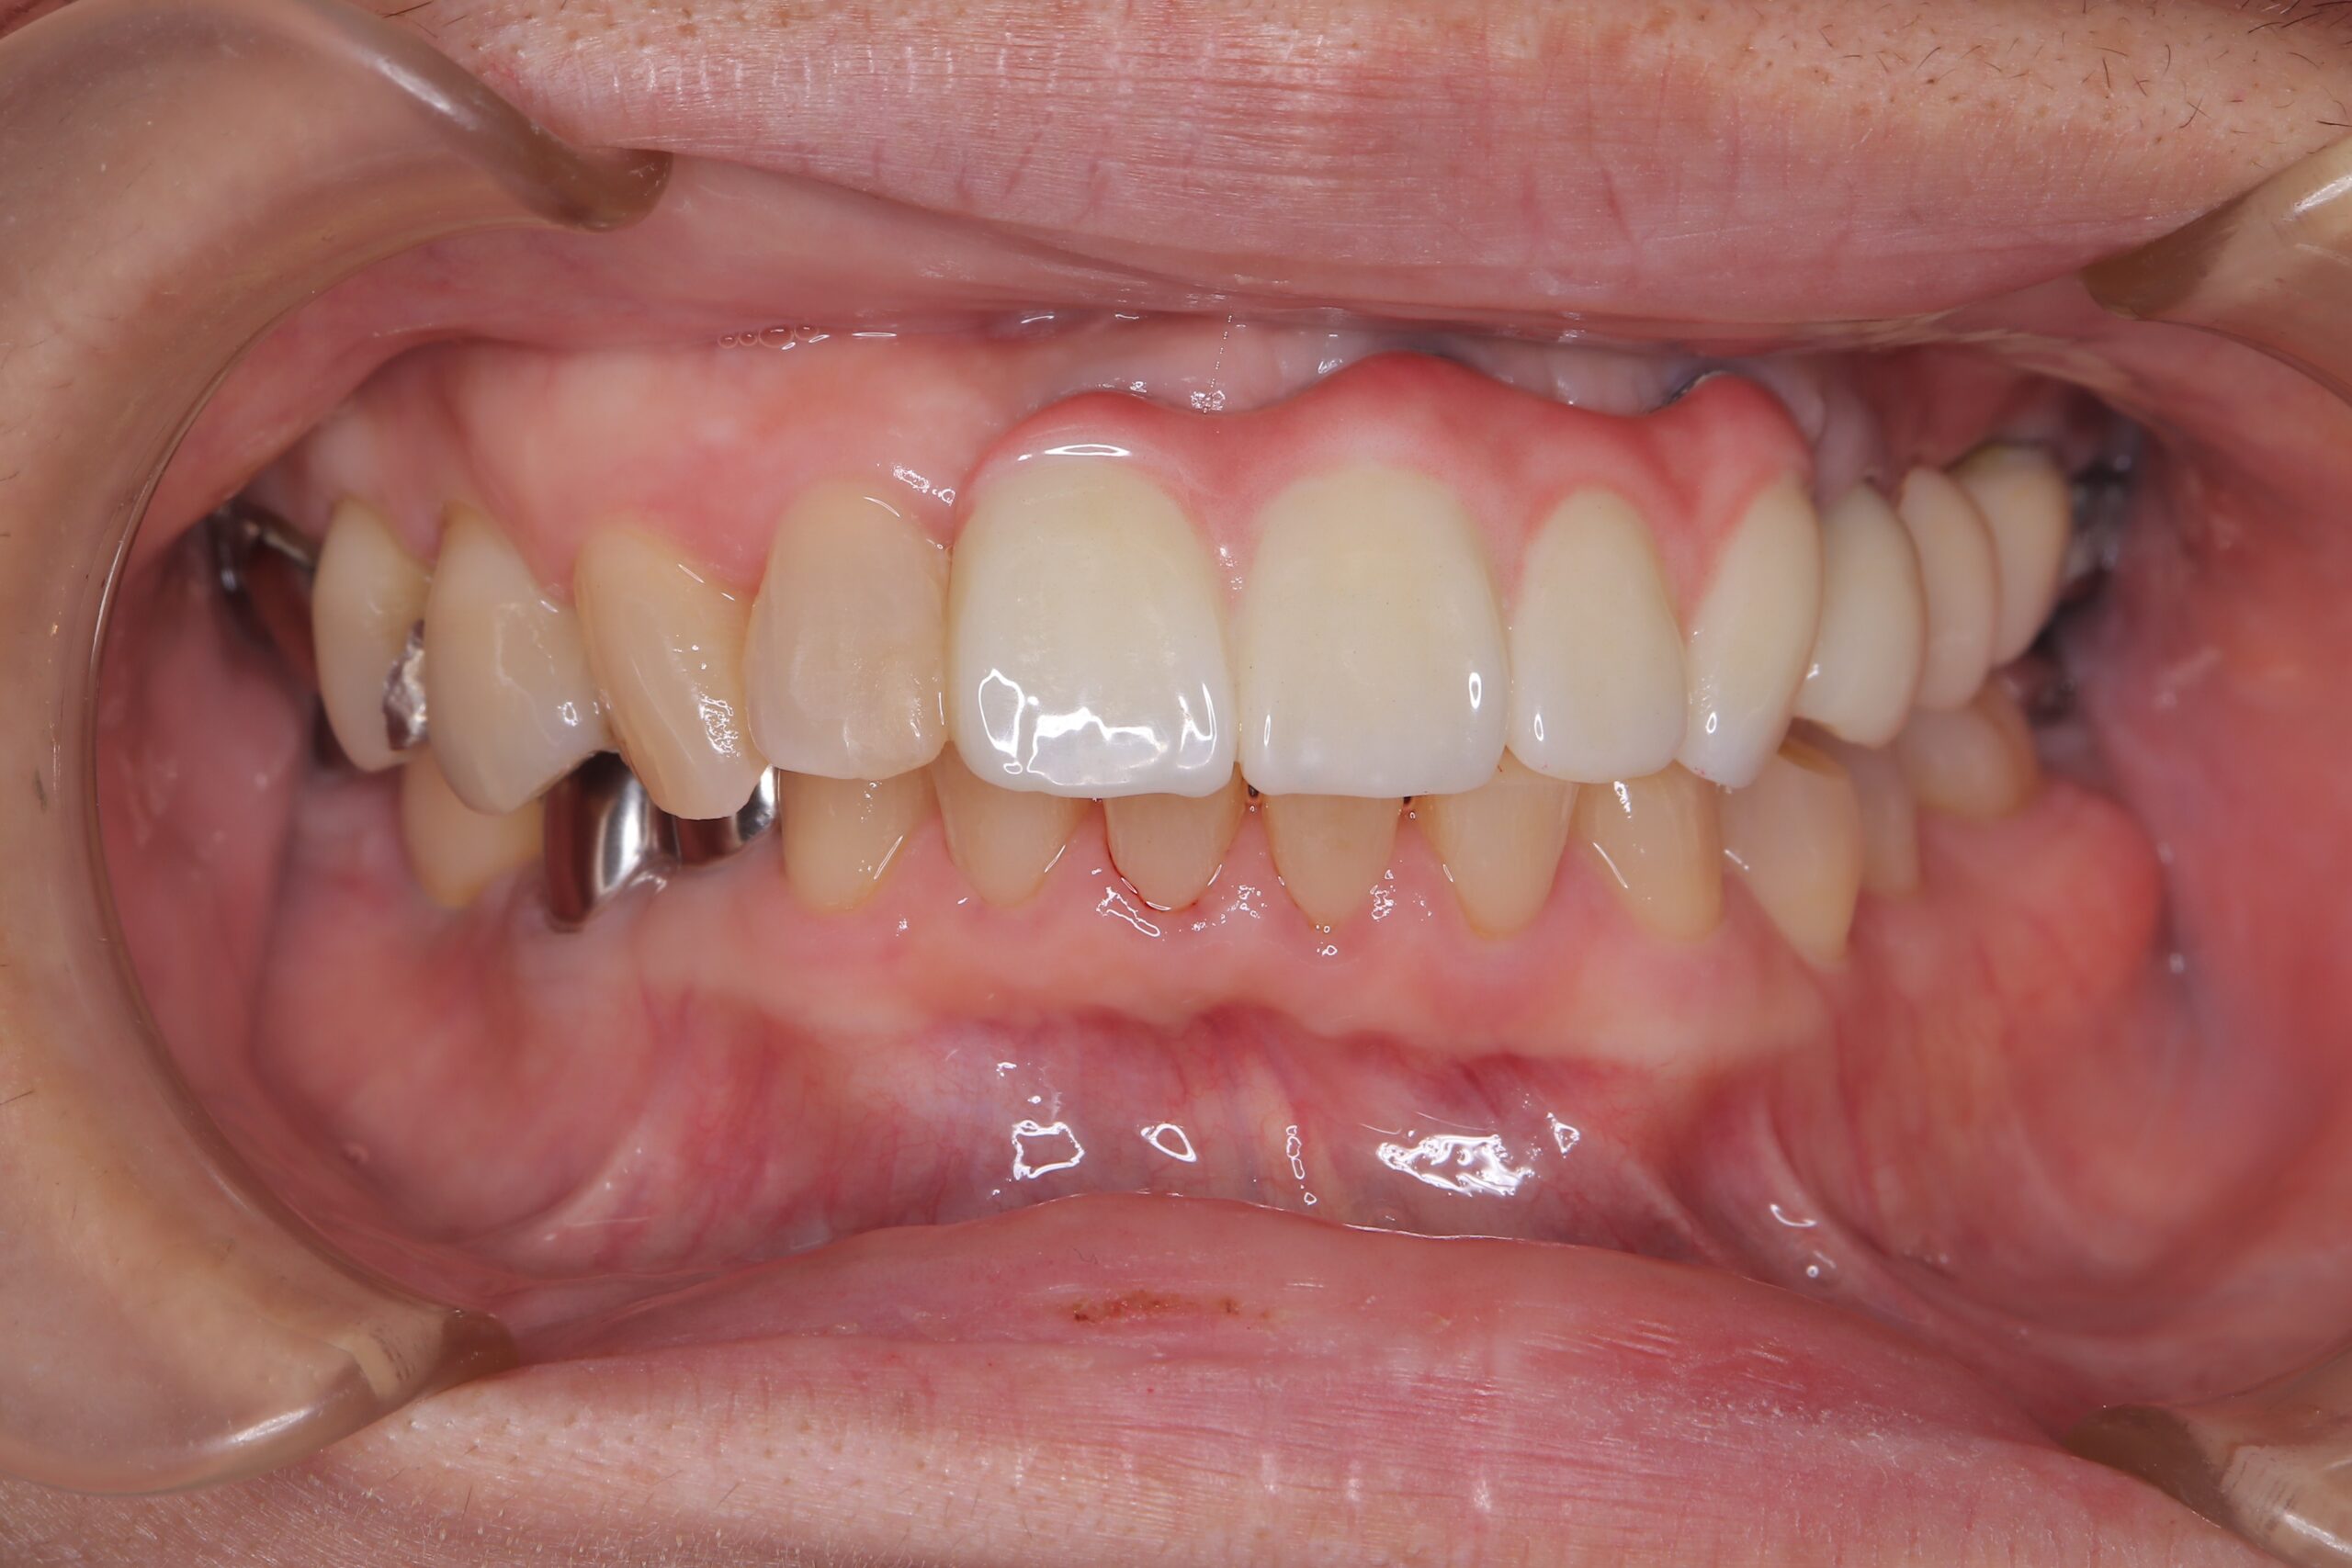

治療後

正面観